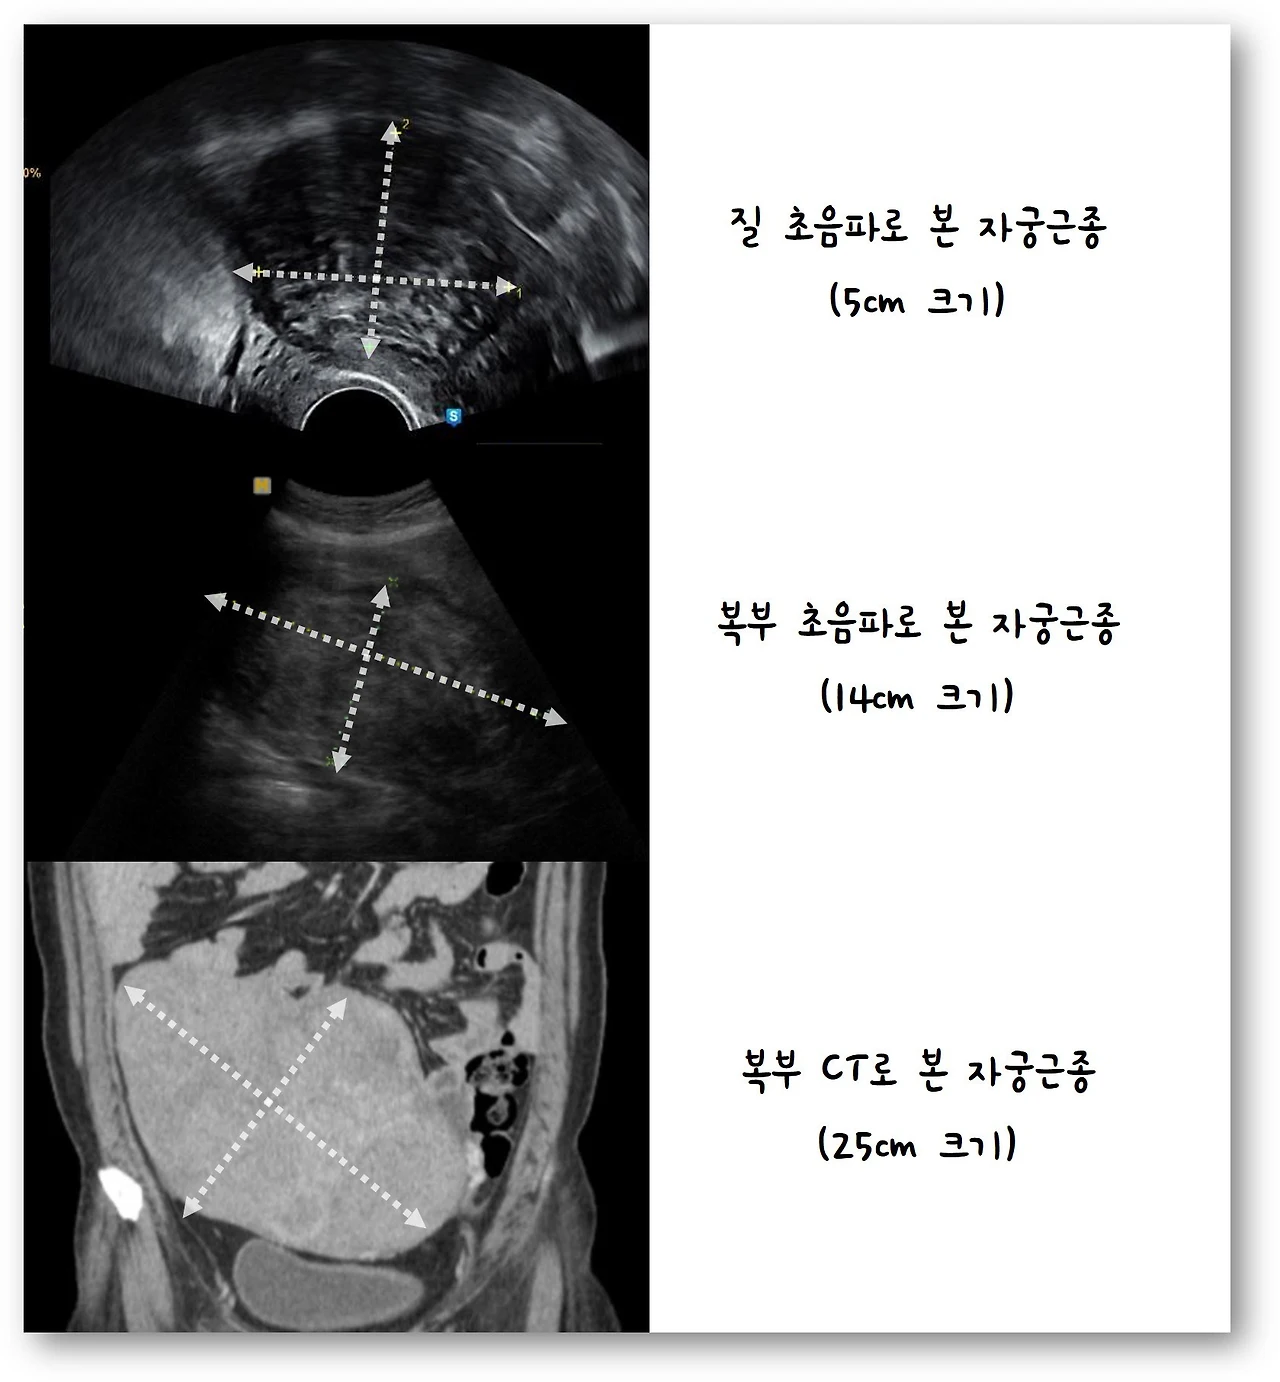

특별한 이유가 없다면 질을 통해 초음파를 시행하게 되고, 일정 수준보다 크기가 큰 자궁근종의 경우에는 자궁과의 위치관계를 확인하기 위해서 복부를 통해 자궁근종을 확인하기도 합니다. 크기가 20~30cm 보다 큰 경우에는 정확한 진단 및 주변 장기와의 위치관계를 확인하기 위해 MRI와 CT와 같은 영상검사도 같이 시행하기도 합니다.

%EC%9E%90%EA%B6%81%EA%B7%BC%EC%A2%85%20%EC%B4%88%EC%9D%8C%ED%8C%8C.jpg?zoom=1.25&w=640&ssl=1